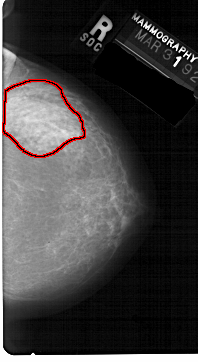

A_1599_1.RIGHT_MLO

RIGHT_MLO LINES 5326 PIXELS_PER_LINE 2716 BITS_PER_PIXEL 12 RESOLUTION 43.5 OVERLAY

FILE: A_1599_1.RIGHT_MLO.OVERLAY

TOTAL_ABNORMALITIES 1

ABNORMALITY 1

LESION_TYPE MASS SHAPE ASYMMETRIC_BREAST_TISSUE MARGINS OBSCURED

ASSESSMENT 4

SUBTLETY 1

PATHOLOGY BENIGN_WITHOUT_CALLBACK

TOTAL_OUTLINES 1

BOUNDARY